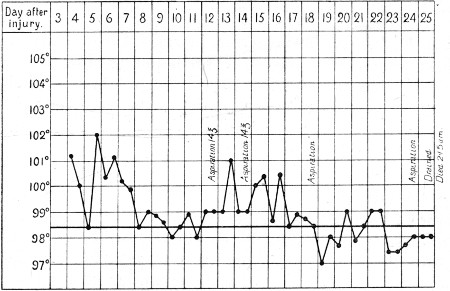

2. Case of Hæmothorax with Recurrent Hæmorrhages 395

3. Primary and Secondary Rises of Temperature in Hæmothorax, Recovering Spontaneously 402

4. Secondary Rise of Temperature in Hæmothorax 403

5. Falls of Temperature in Hæmothorax following Paracentesis 404

6. Secondary Hæmothorax, Spontaneous Fall of Temperature 405